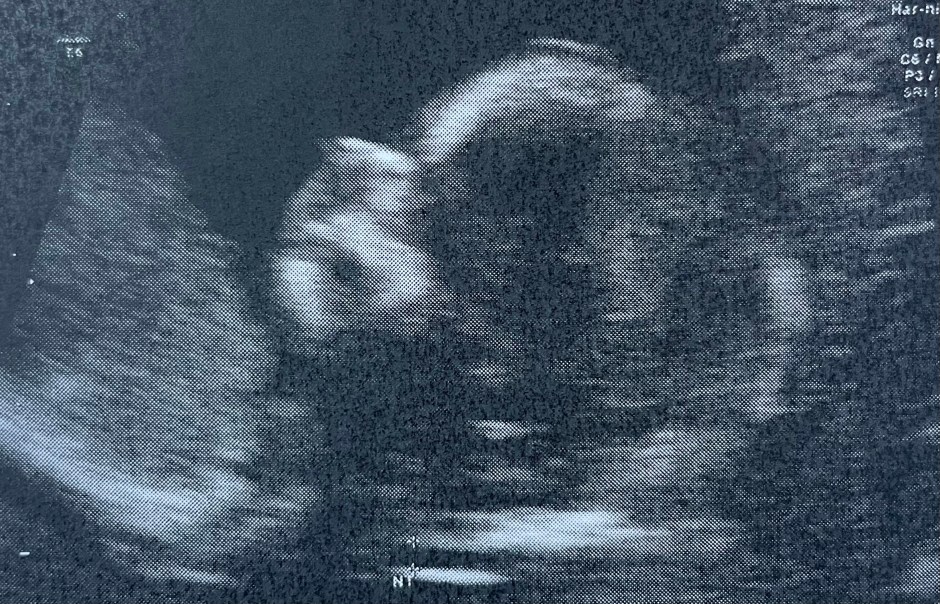

However! Calling a post “turning a corner” and then complaining for three full paragraphs is a smidge incongruous, but I am getting to that part, I promise! So, as hinted at, during the past few days I have felt like maybe I am turning a corner. Maybe it’s because I’ve reached the magical 14 weeks when everyone says I will start to feel better. I honestly don’t feel particularly more energetic (the evenings still find me squished into a corner of the couch, trying to get into a position that does not trigger my gagging-on-nothing reflex) but I do feel slightly better, nonetheless. It might also be because the Bean’s NT scan was last week, and we also received the NIPT (non-invasive prenatal testing) results: all point to low-risk for the three most common trisomies. Perhaps that was weighing on me more than I realized. (In a miraculous turn of events, there were also two other items of good news in the very same day: my father’s 3-month check for the cancer he was diagnosed with last year came back all clear, and my best friend from college was accepted into the next stage of her graduate training.) A collective sigh of relief on many fronts.

It could also be that the NT scan would honestly be quite fun if it weren’t so serious: they have to get the baby into the right position in order to take the relevant measurements, and since little beans can react to external stimuli by this point in their development, they jiggle the ultrasound probe around on your belly, and you can watch your little bean wiggling around in response inside. The internet informs me that Bean is currently the size of a lemon, but during that scan they truly start to look like a real baby, arching and flexing and throwing limbs around, one can only assume in annoyance at being disturbed. This prompted a few moments of of picturing myself with an actual baby: for some reason, this has not happened to me very often yet during this pregnancy (I’ve primarily experienced it as a loss of independence and sense of self, instead), but when I do picture myself with an actual baby, I remember that I really like babies. I always have. Little loaf of bread newborns, and giggly squiggly 4-6-month-olds, and starting to crawl, and starting to walk, and 12-18-month-olds and their little emerging personalities and how all they want in life is for you to get down on the floor and play and snuggle. Teaching them to use a spoon… and not jump off the furniture… (I once worked in a daycare, and both spoons and the furniture acrobatics are prominent in my memories of that time). I declared to my mother that I wanted a baby of my own when I was about seven, and was crushed when she told me I needed to wait twenty years or so. I felt so ready for this step when we started trying in summer of 2020. So where is all of that now?

Okay. Now instead of closing on the exceedingly dramatic imagery of nursing home denizens on stretchers, I can close on the tragicomic mental image of my ill-fitting undergarments. I wish you all a splendid day, and I leave you Bean’s 13-ish week head for your enjoyment in the header image – Bean is starting to look like a real human!